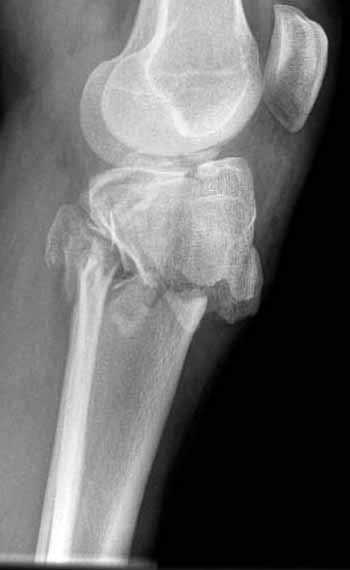

Двухколоннный перелом тибиал плато с вовлечением проксимального диафиза. Внутрисуставной компонент без смещения, и такой перелом можно лечить любым из описанных методов, о которых говорят наши коллеги.

Как понял, аппарат Илизарова не рассматривается предпочтительным для фиксации методом, хотя на фоне отека было бы идеальным для данного перелома. Для пластины требуется идеальная кожа, иначе наличие “суперсовременных имплантов” не поможет, и могут развиться серьезные осложнения.

В основном пластины рассчитаны на латеральную поверхность, потому что с латеральной стороны больше мягкотканая подушка, а также через латеральную колонну проходит ось конечности, что немаловажно в удержании оси от деформации.

Для изолированных переломов медиального тибиал плато, фиксацию можно провести “медиальной пластиной”. Некоторые компании, например Smith & Nephew делают медиальные и медиально-задние пластины, но они мягкие, и легко можно создать нужный контур. Жесткость создается за счет фиксации жесткими пластинами, например экстра артикулярной пластиной для дистального плеча от Synthes. Медиальный доступ тоже не из легких, надо работать между pes and medial gastroc.

Частая ошибка, когда фиксацию двух колонного перелома проводят одиночной пластиной, т.е с одной стороны, и такая фиксация не удерживает, происходит вторичноое смещение. Необходимо нейтрализовать второй пластиной или дополнительным наружным фиксатором.

В приложении этапы фиксации Both Column Fx и пластиной Synthes для плеча при переломе медиального мыщелка.